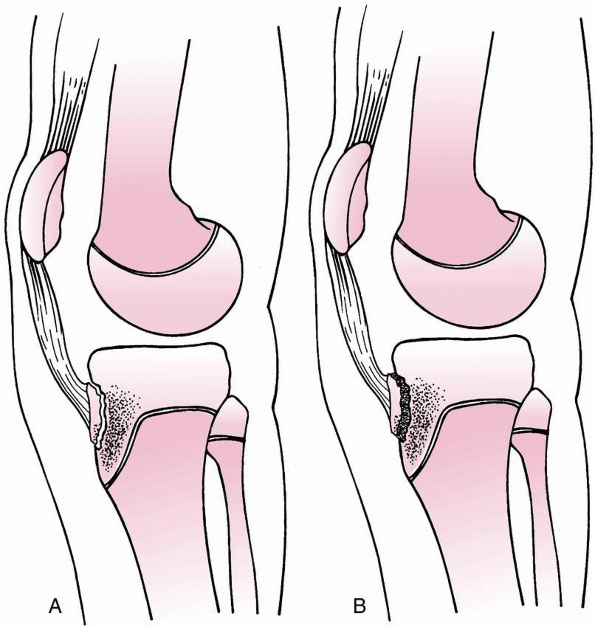

metaphysis may stretch and tear the tethered popliteal artery (Figs. 23-17 and 23-18).

FIGURE 23-17

Posterior displacement of the epiphysis following fracture-separation at the time of injury can cause arterial injury. In addition, a posteriorly displaced fragment can cause persistent arterial occlusion by direct pressure. (Reprinted with permission from Skaggs DL, Flynn JF. Trauma about the knee, tibia, and foot. In Skaggs DL, Flynn JF, eds. Staying out of Trouble in Pediatric Orthopaedics. Philadelphia: Lippincott Williams & Wilkins; 2006.) |